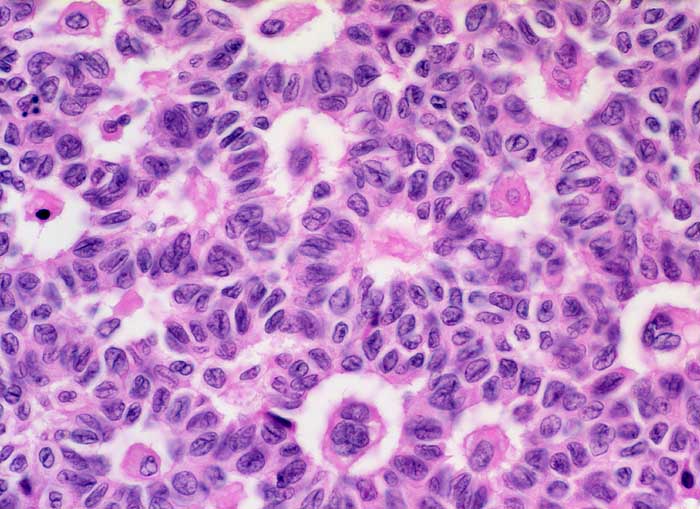

PathoPic – image database / PathoPic ID 5333 - Granulosazelltumor vom adulten Typ, Call Exner Körperchen

Granulosazelltumor vom adulten Typ, Call Exner Körperchen

maligner Tumor

Ovar

Die Tumorzellen zeigen eine Positivität für Inhibin und CD99, sind jedoch negativ für EMA.

Ovarial-Tumor links -> Adnexektomie links. Frage: Dignität? CA-125 im Normbereich.

Die Call Exner Körperchen gleichen unreifen Follikeln und sind ein guter Hinweis auf einen Granulosazelltumor

Histologie

400